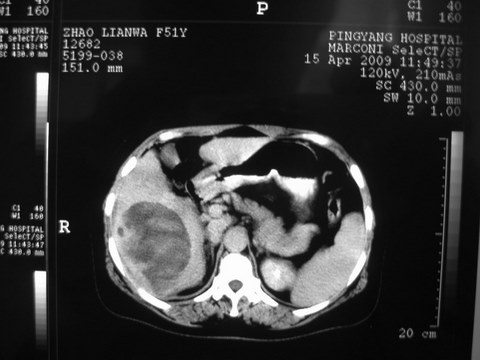

患者 女 51岁 两天前感觉上腹疼,无明显诱因,b超示肝右叶囊实性占位,边缘清楚,其内回声不均匀,ct增强如图,大家看看是什么 ,病人一年前及两月前b超检查只是提示胆囊炎

外院术后,证实肝癌合并出血

特点:1,病灶发展迅速,(2月前正常)[br] 2,囊实性,且并边界清晰光滑,呈右后叶赘生性。囊性区无强化,实性部分较多轻度强化,边界欠清。考虑囊腺癌或囊腺瘤。

出病理 中分化肝细胞癌合并出血